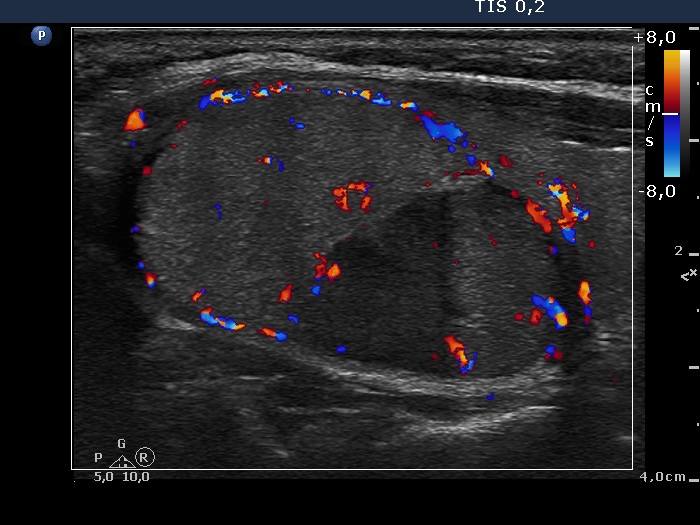

The echogenicity of the nodule - case 2158 (ultrasonographic picture 6)

Left lobe, longitudinal view, color Doppler mode. The lesion shows perinodular blood flow and signs of intranodular vascularization.